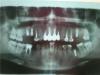

Серж 85 Опубликовано 8 июля, 2013 Поделиться Опубликовано 8 июля, 2013 (изменено) Здравствуйте! Скажите пожалуйста можно установить виниры на верхние зубы с пломбами,или придется ставить коронки? P.S.Снимок прилагается,вот ссылка: http://s50.radikal.ru/i130/1307/7d/67ee3beffc93.jpg Изменено 8 июля, 2013 пользователем Серж 85 Ссылка на комментарий

Art 7 Опубликовано 8 июля, 2013 Поделиться Опубликовано 8 июля, 2013 У Вас полный треш с жевательными зубами а вы виниры делаете?)скорее всего можно только на клыки, судя по панораме. Остальные в коронки. 3 Ссылка на комментарий

IvanK Опубликовано 8 июля, 2013 Поделиться Опубликовано 8 июля, 2013 Есть более качественные снимки? Думаю, что по большей части будут коронки..Боковые отделы планируете протезировать? Может начать с них?.. Ссылка на комментарий

Серж 85 Опубликовано 9 июля, 2013 Автор Поделиться Опубликовано 9 июля, 2013 Уважаемые врачи!!! Снимок старый..,импланты мне не давно поставили: 4 наверху с операцией закрытый синус лифтинг,и 1 в низу.Зимой будут ставить абатмент и коронки.У меня беда в том,что в клинике где ставили циркониевые коронки,не устанавливают виниры.Подскажите как мне поступить в данной ситуации; Депульпировать 3 зуба с пломбами с последующей установкой коронок,а потом идти в другую клинику,и просить,что б поставили мне на клыки виниры? В другой клинике где ставят виниры смогут подобрать по цвету остальных коронок? Ссылка на комментарий

Серж 85 Опубликовано 22 июля, 2013 Автор Поделиться Опубликовано 22 июля, 2013 (изменено) Здравствуйте,я решил ставить коронки на клыки и рядом стоящие зубы,скажите пожалуйста,стоит ли рисковать ставя коронки на живые клыки,или все таки их депульпировать?И если,протезист повредит пульпу,можно будет просверлить циркониевую коронку? P.S.Новые снимки прилагаю. Изменено 22 июля, 2013 пользователем Серж 85 Ссылка на комментарий